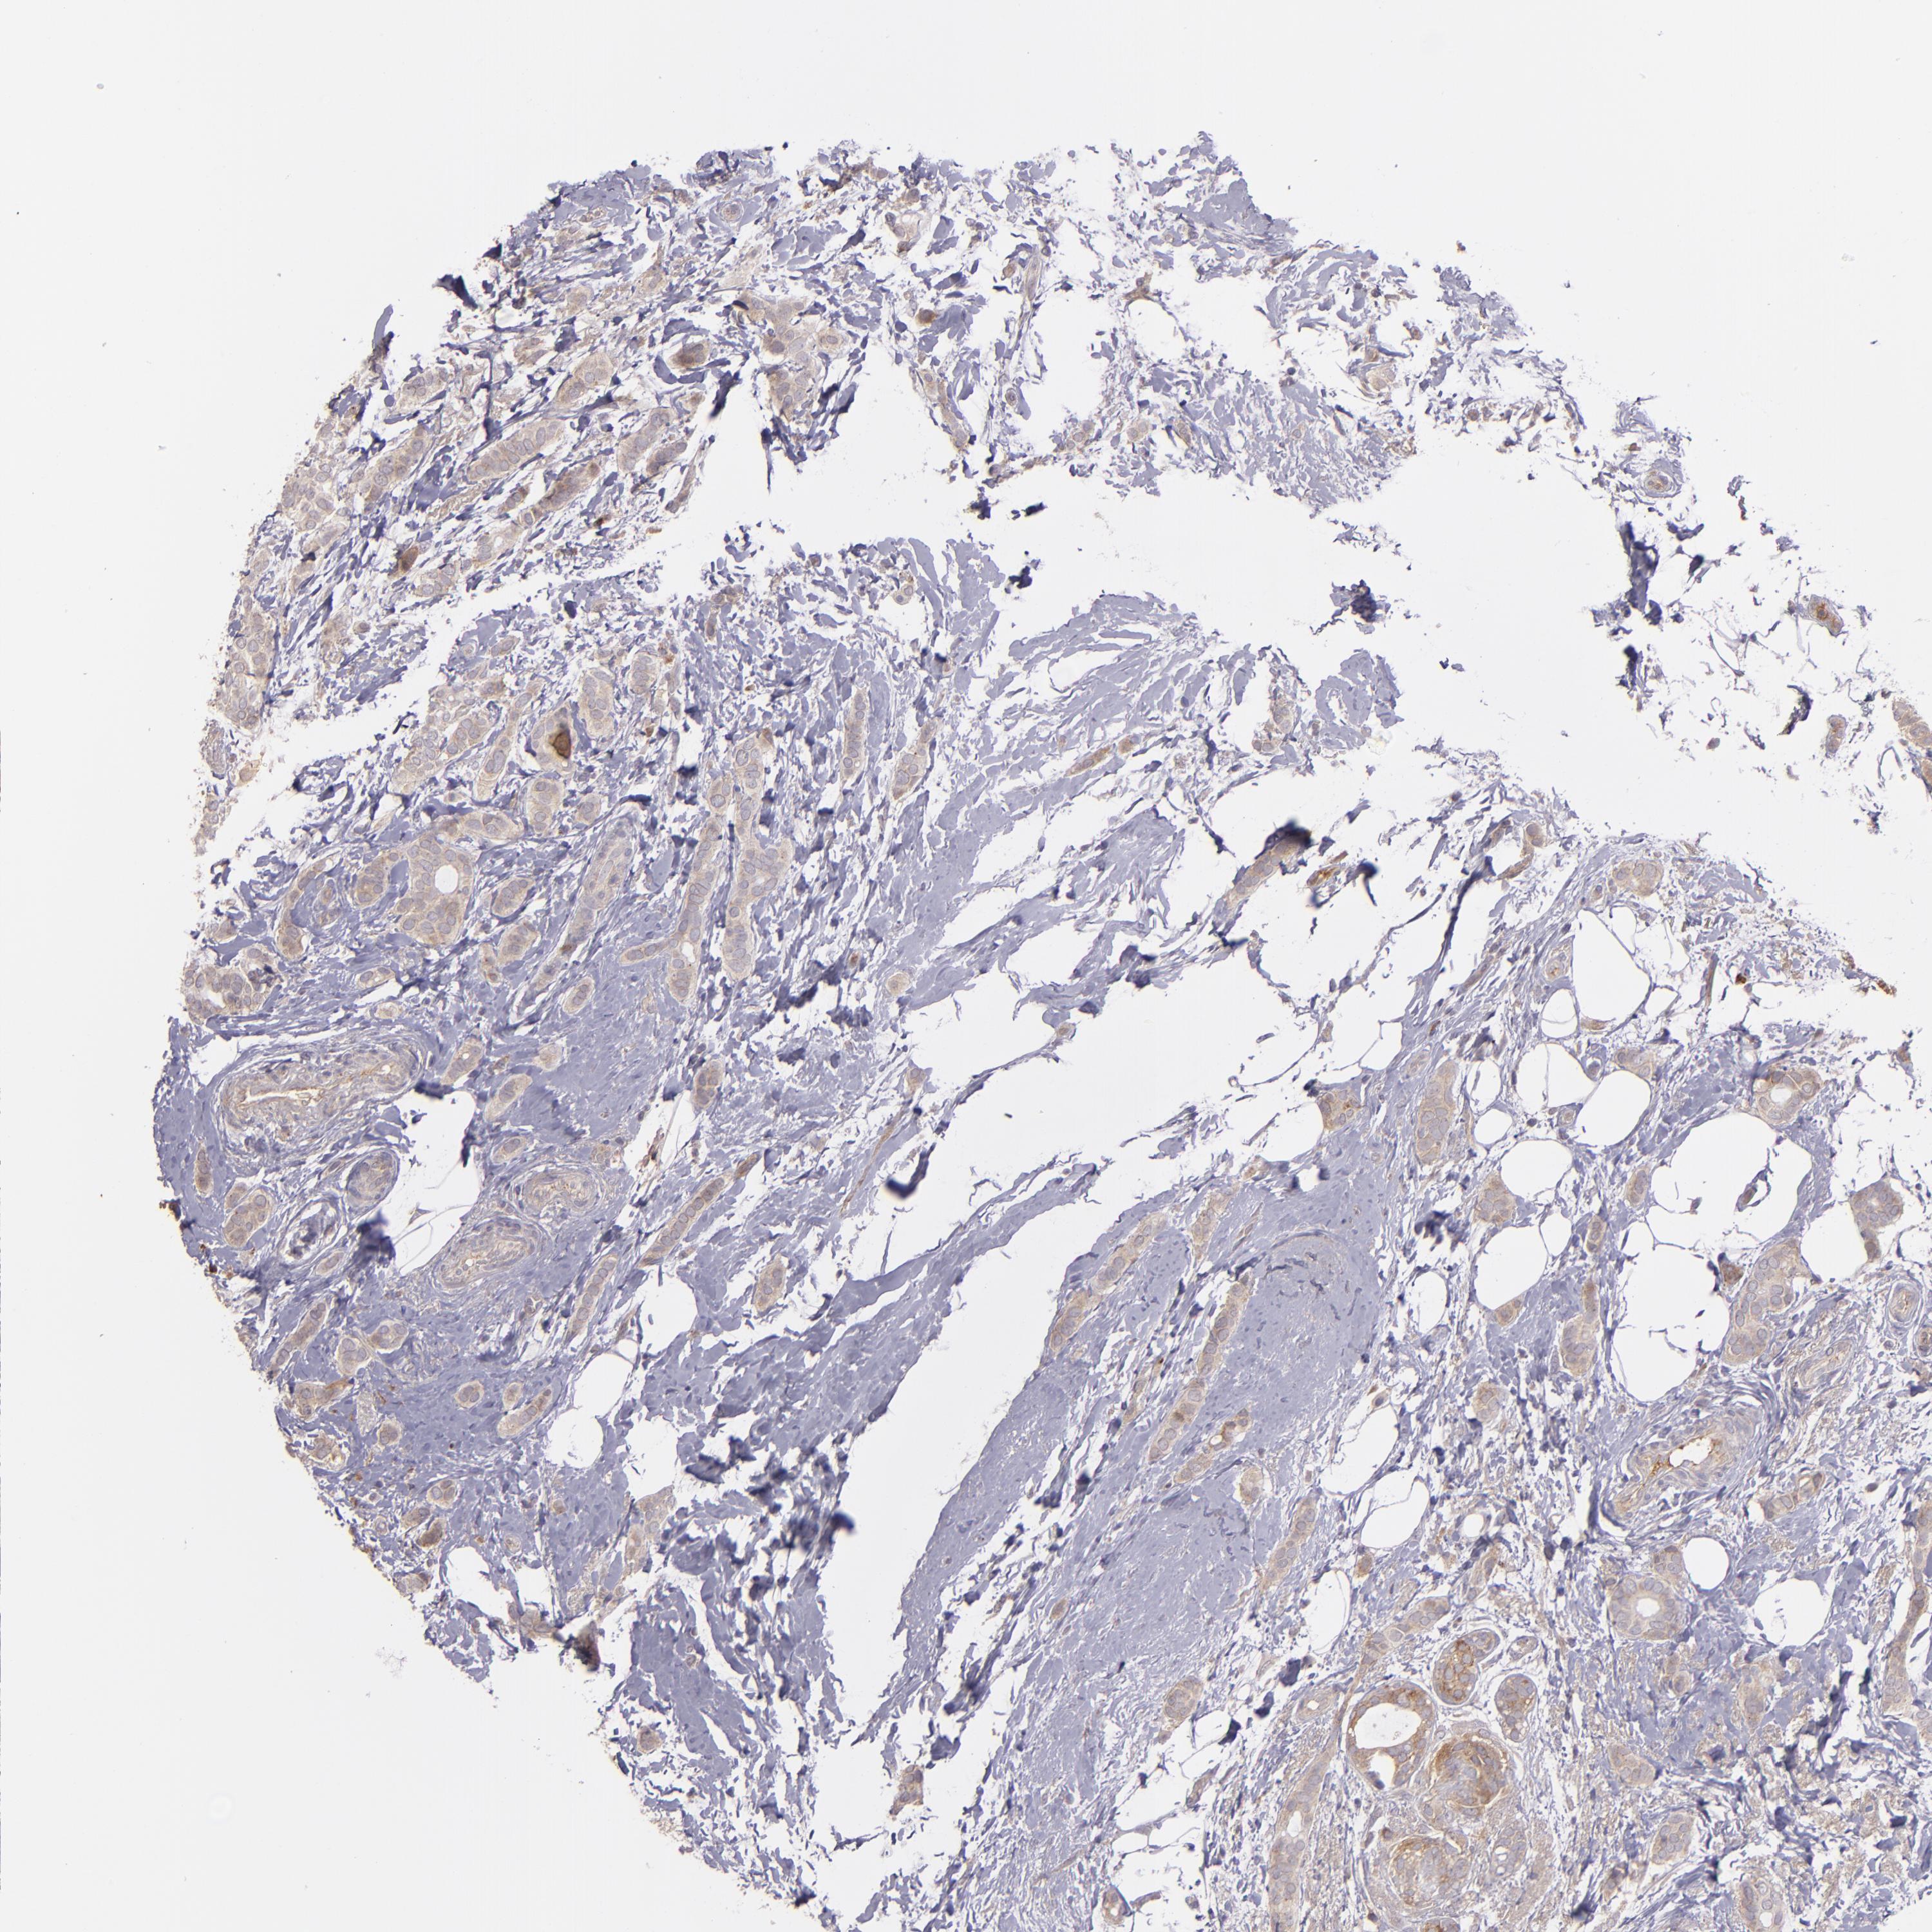

CANCER BREAST CANCER Show tissue menu

BRCA TCGA BRCA VALIDATION PROTEIN EXPRESSION